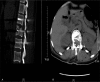

Outcomes: There was an immediate improvement in her neurological function in just 1 day after 2-stage operation. During the 6-month follow-up period, her neurological functions gradually recovered, and she was able to defecate and urinate. At the last follow-up visit, her spinal cord function was assessed to be at Frankel grade D.

Lessons: PPSF plus TESCD can achieve complete spinal cord decompression, promote neurological recovery, and is therefore an effective method for the treating lumbar burst fractures with severe neurologic deficits.